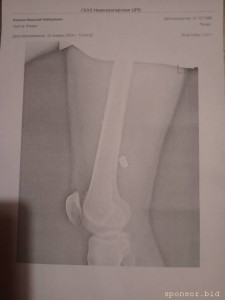

Рентген от 23.01.2024г. В госпитале не доглядели оставили осколок, который доставляет не малый дискомфорт при нагрузке